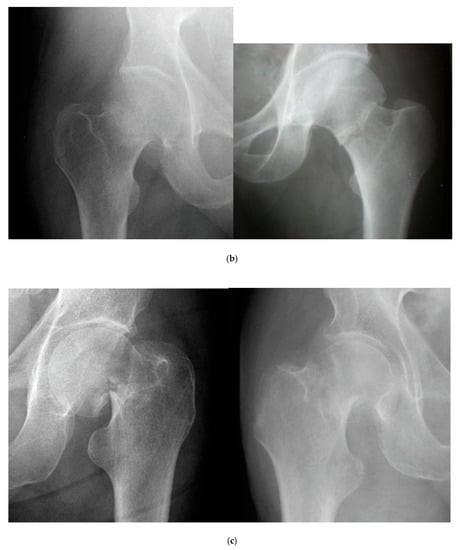

2.1. Classification of Femoral Neck Fractures

- Stage I: incomplete fracture; nondisplaced, valgus impacted

- Stage II: complete fracture; nondisplaced

- Stage III: complete fracture; partially displaced

- Stage IV: complete fracture; fully displaced